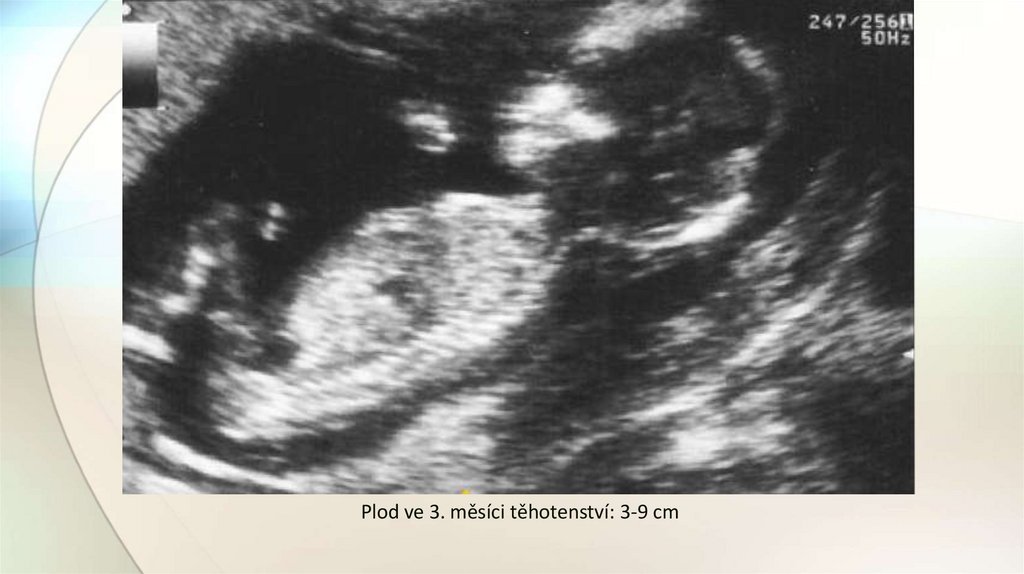

20. Fetální období

• začíná 9. týdnem a končí porodem.

• organogeneze prakticky skončila

v embryonálním období.

• nyní orgány rostou, vyvíjejí se a

začínají fungovat.

• plod ve 3. měsíci těhotenství 3-9 cm

Plod ve 3. měsíci těhotenství: 3-9 cm